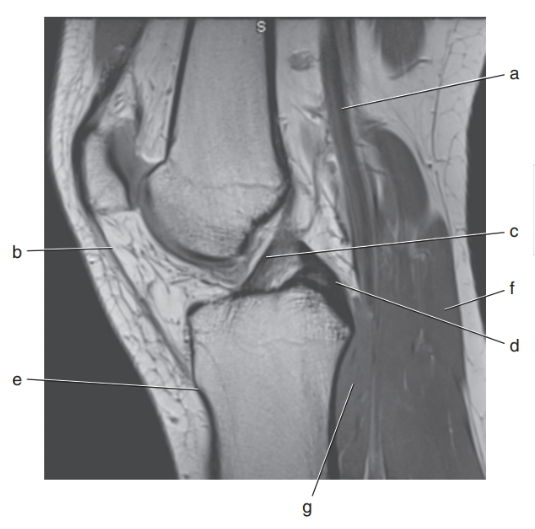

What is c ?

anterior cruciate ligament

lateral meniscus

What is d ?

posterior cruciate ligament

What is g ?

spinal cord

In what orientation would a tear of the collateral ligaments of the knee be best visualized?

coronal